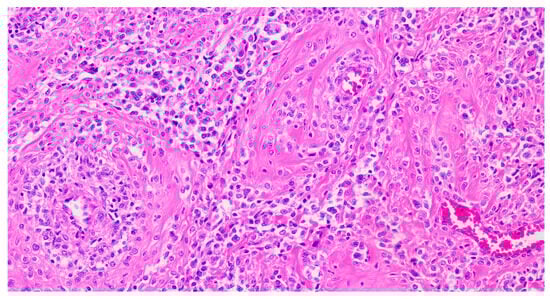

Histologically, PEComas are composed of epithelioid cells and, less frequently, spindle cells. Epithelioid cells exhibit clear to eosinophilic granular cytoplasm and are typically arranged in dyscohesive nests surrounded by delicate, thin-walled blood vessels and/or in solid sheets (Figure 2). In contrast, spindle cells often form fascicles. Additional features may include perivascular distribution, multinucleated cells, lipid-rich or rhabdoid cytoplasm, and stromal hyalinization. Tumors may display expansile, permeative, or infiltrative growth patterns. Both cell types can show variable degrees of cytological atypia and mitotic activity, and melanin pigment may also be present [24].

Figure 2.

Hematoxylin–eosin-stained section from a uterine PEComa. Epithelioid cells with clear to eosinophilic cytoplasm in a radial/perivascular distribution, with stromal hyalinization (20× magnification).

PEComas are characterized by the immunoexpression, among others, of both melanocytic markers (HMB-45, Melan-A, MiTF, and PNL2) and myoid markers (desmin, smooth muscle actin, muscle-specific actin, myosin, and calponin). HMB-45 (more specific) and Cathepsin K (more sensitive) are expressed in virtually all PEComas, ranging from diffuse staining to isolated positive cells (Figure 3). Melan-A staining and MiTF are expressed with variable intensity in more than two-thirds of cases, and they are usually focal and less extensive than HMB-45 [6]. MiTF tends to be weak and lacks specificity, and PNL2 shows variable cytoplasmic expression. Except for TFE3-rearranged tumors, the expression of at least one smooth muscle marker is typically strongly positive (SMA being the most expressed). Overall, melanocytic markers are predominantly expressed in epithelioid cells, while myogenic markers are more commonly seen in spindle cells, but overlaps may occur [15].

Figure 3.

Immunostaining of HMB-45 in a uterine PEComa. Patchy granular cytoplasmic staining for HMB-45 (40× magnification).